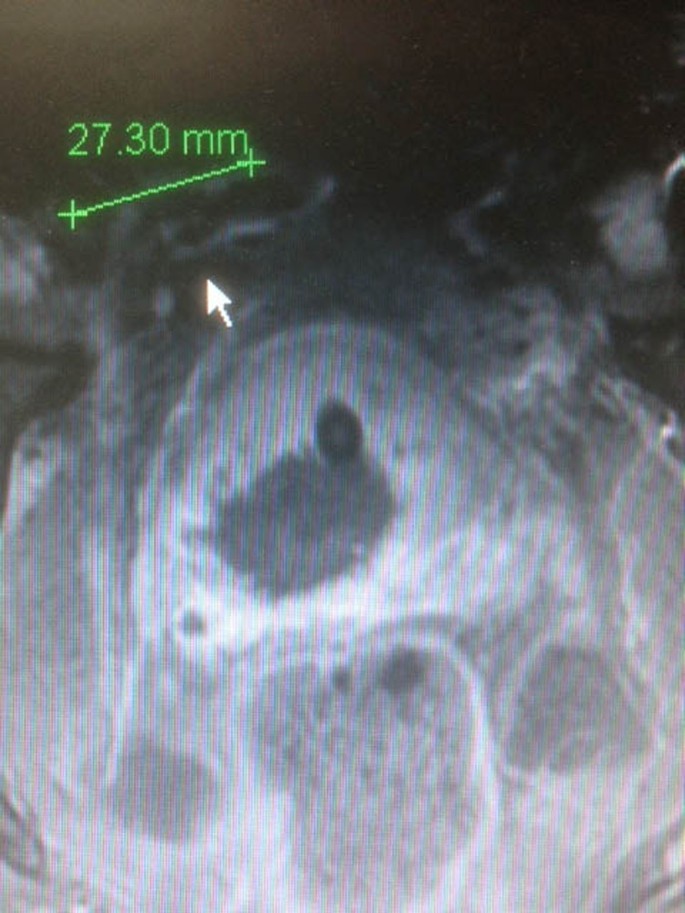

Material and method: Focal One® is a device designed for the focal therapy of Prostate Cancer combing the necessary tools to visualize, target, treat and validate the focal treatment. MR volumes are imported through the hospital’s network. The operator defines the contours of the prostate and the regions of interests that have been confirmed as prostate tumors. The same contouring of the prostate is performed on the live ultrasound volume acquired by the transrectal probe. The software proceeds to an “elastic fusion”: the live Ultrasound volume is considered as the reference volume and the MR volume is smoothly deformed so the 3D contour of the prostate on the MR volume matches perfectly the contours of the prostate on the Ultrasound Volume. The same 3D elastic transformation is applied to the ROIs initially indicated on the MR image so they appear at the adequate position on the live Ultrasound Image, guiding the planning process. The Focal One is equipped with a new generation of HIFU probe able to electronically vary the focal point along the acoustic axis using a HIFU multi-element phase array transducer. During the HIFU energy delivery process, the operator sees a live ultrasound image of what is being treated and, if necessary, can readjust the treatment planning. At the end of the treatment process, a Contrast-enhanced Ultrasound volume is acquired showing the de-vascularized areas.

Teen patients with mono focal prostate cancer were treated between March 2013 and January 2014. HIFU treatment process was realized with the Focal One device using a 6 mm safety margin around the tumor. Contrast enhanced MRI is performed at day 2 after HIFU and Control biopsies guided with contrast-enhanced Ultrasound imaging were achieved one month after HIFU inside and in the rime of the treated area.